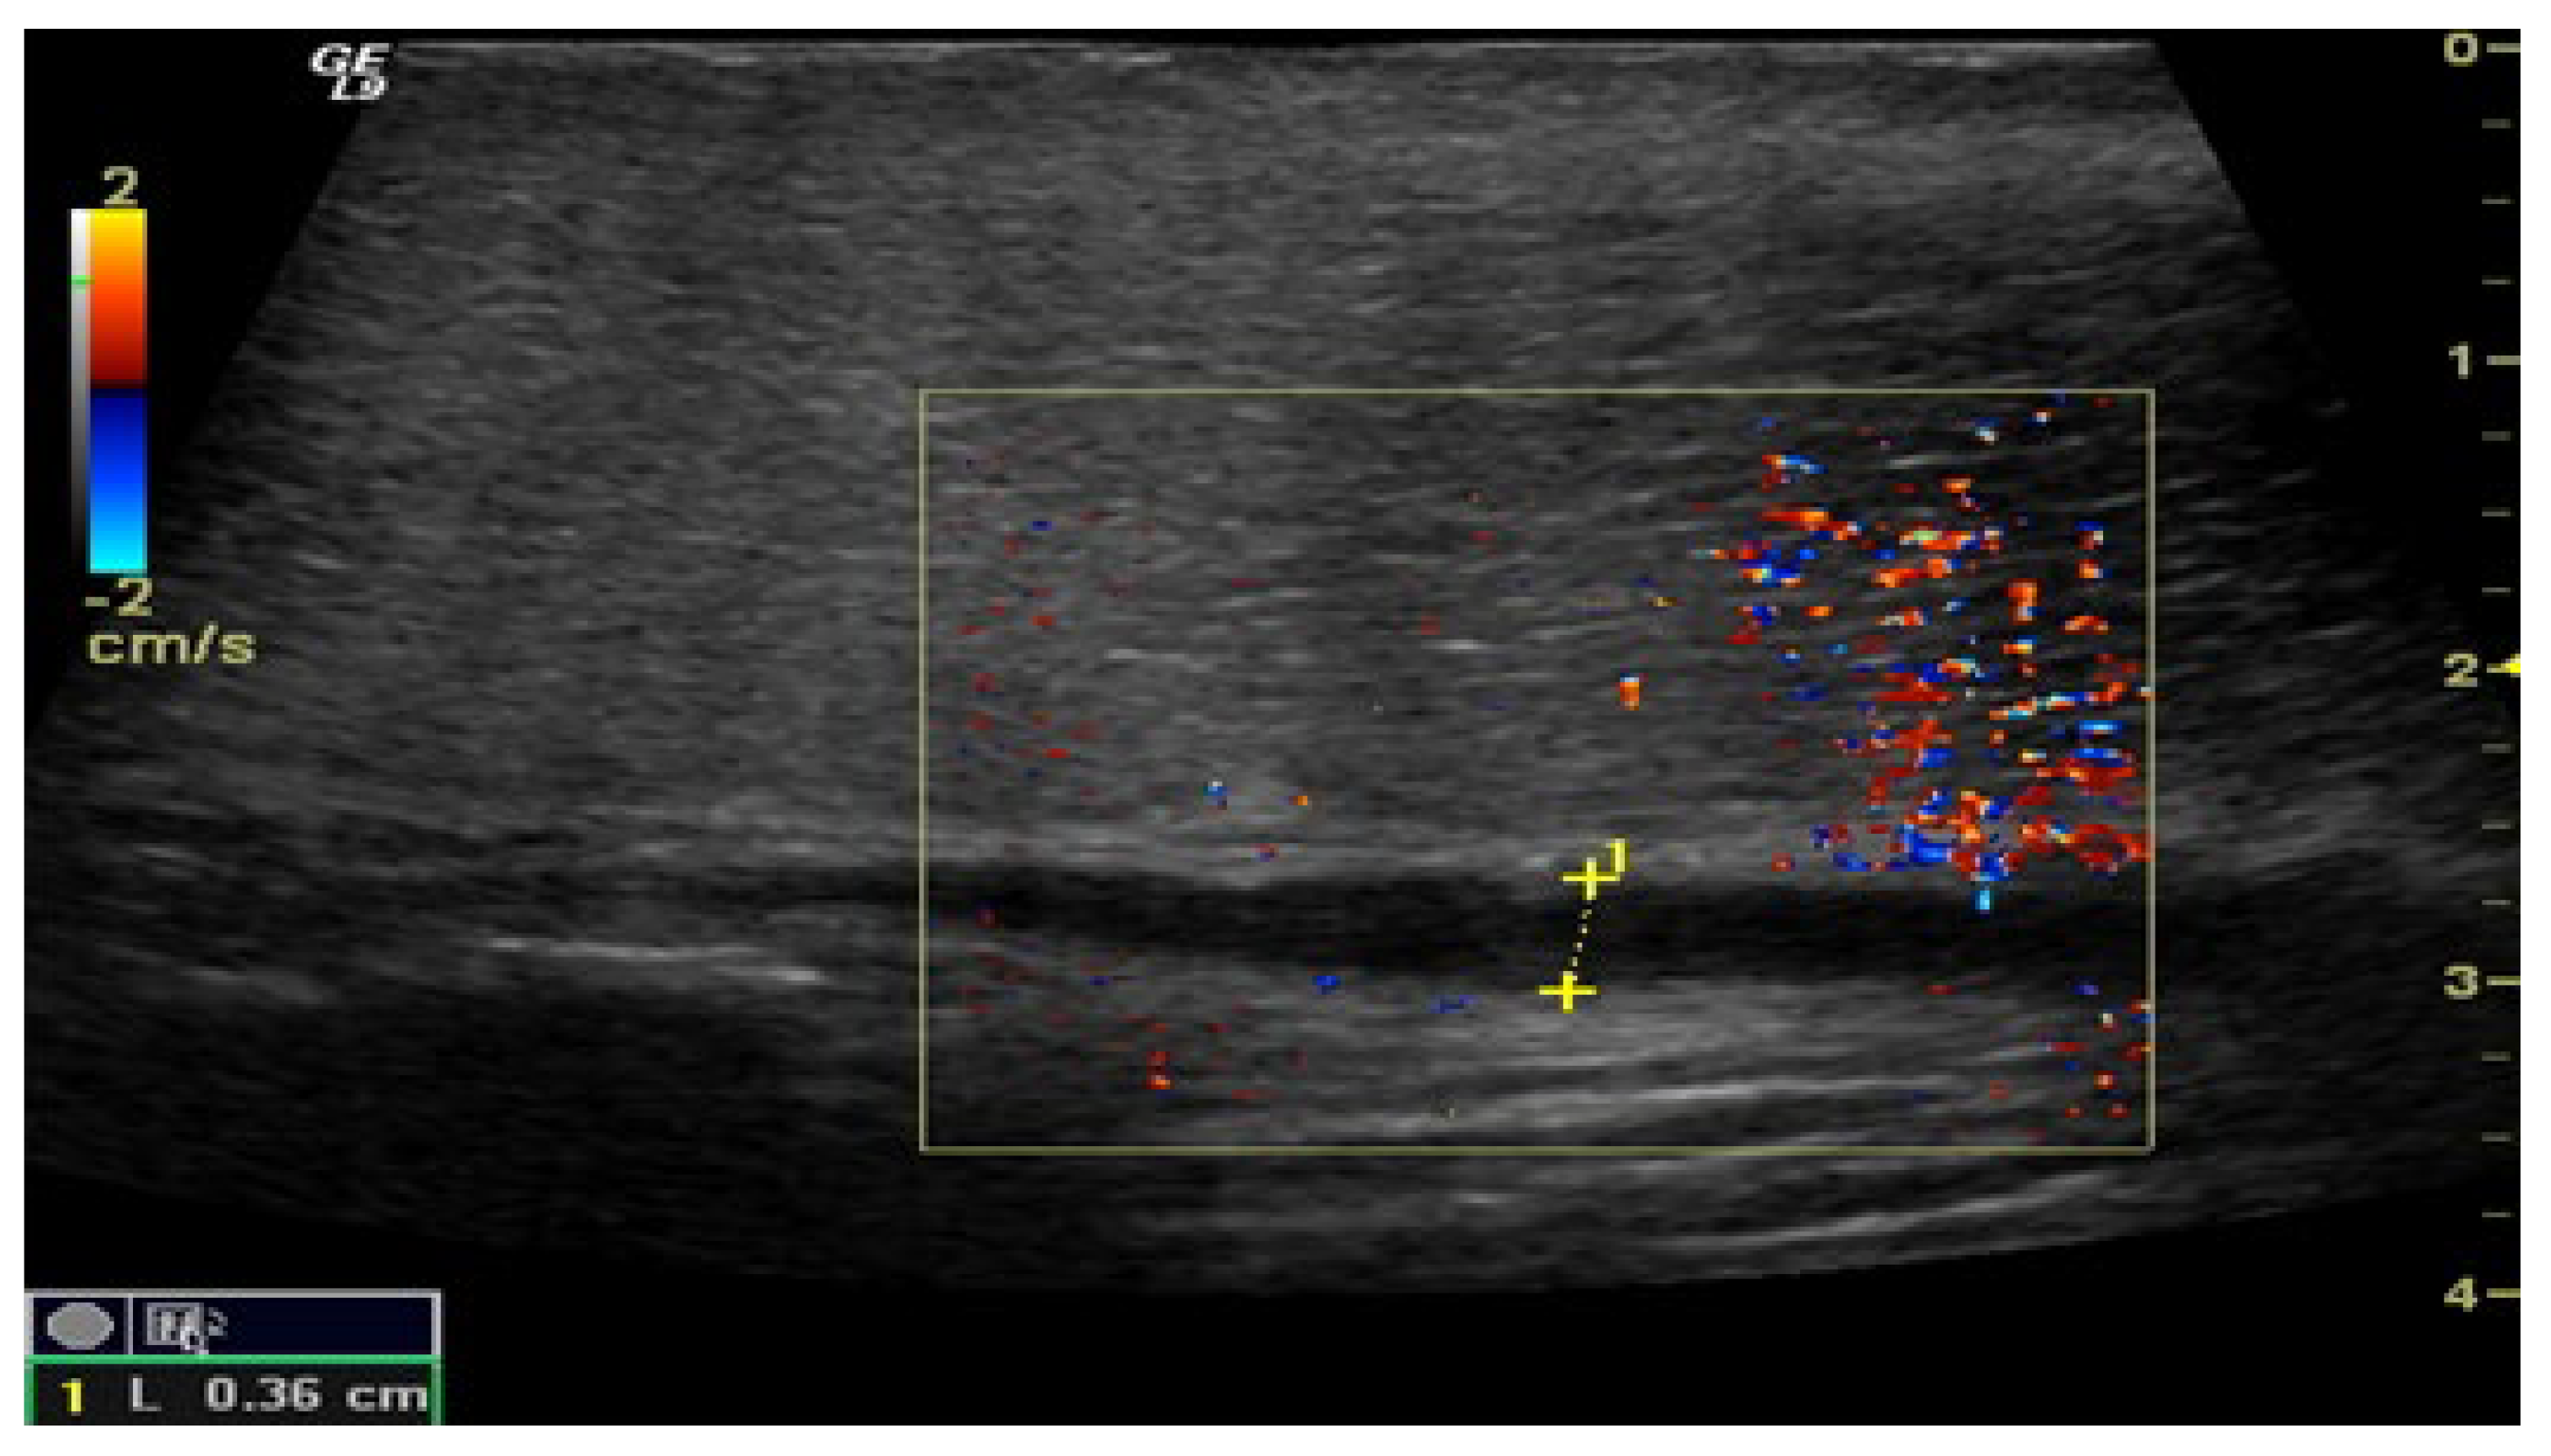

Figure 3.

Penile CDUS during pharmacologically induced erection. Signs of veno-occlusive ED: diameter of the deep dorsal vein is enlarged, indicating venous insufficiency.